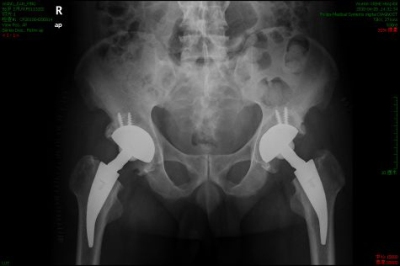

骨闪烁成像显示热区中的冷区,组织活检证实骨坏死,骨闪烁显像显示热区或冷区损害,MRI显示股骨头内低信号点见(图2)。

(图2)MRI 显示股骨头内低信号点双侧股骨头坏死